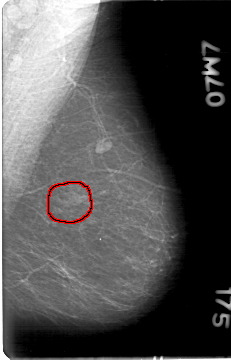

D_4028_1.LEFT_MLO

FILE: D_4028_1.LEFT_MLO.OVERLAY

TOTAL_ABNORMALITIES 1

ABNORMALITY 1

LESION_TYPE MASS SHAPE LOBULATED MARGINS OBSCURED

ASSESSMENT 0

SUBTLETY 4

PATHOLOGY BENIGN

TOTAL_OUTLINES 1

BOUNDARY

LEFT_MLO LINES 5386 PIXELS_PER_LINE 3451 BITS_PER_PIXEL 12 RESOLUTION 43.5 OVERLAY